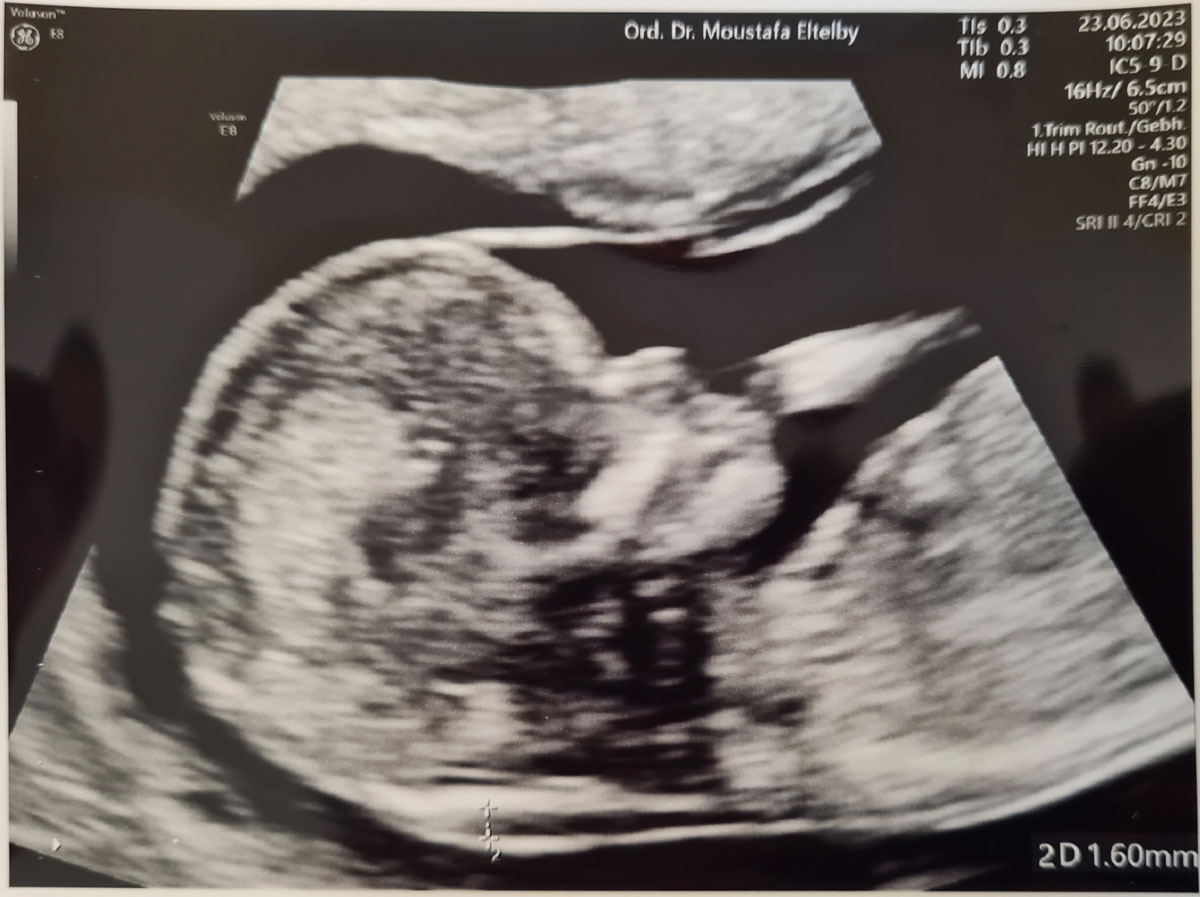

Gängige Methoden sind zum einen die nicht-invasiven, nur außerhalb des Körpers vorgenommenen Untersuchungen wie die Ultraschalluntersuchung (Sonographie), zu denen die Nackentransparenzmessung, die Nasenbeinmessung (in der 12. bis 14. Schwangerschaftswoche), die Fetometrie, der Feinultraschall, die Doppler-Sonographie, der 3D-Ultraschall und der 4D-Ultraschall gehören. Auch die Untersuchungen von Hormonkonzentrationen im mütterlichen Blut (serologische Untersuchungen) wie beispielsweise der Triple-Test, der Quadruple-Test und als Kombination beider Methoden das Erst-Trimester-Screening (ETS, eine Untersuchung im ersten Schwangerschaftsdrittel) und das integrierte Screening (kombinierte Untersuchung der biochemischen Serum-Parameter zur Risikoermittlung für fetale Chromosomen- und Verschlussstörungen) gehören zu den nicht-invasiven Methoden. Invasive, das heißt innerhalb des Körpers vorgenommene Untersuchungen der Pränataldiagnostik sind die Chorionzottenbiopsie (CVS), die Amniozentese (AC) und die Nabelschnurpunktion.